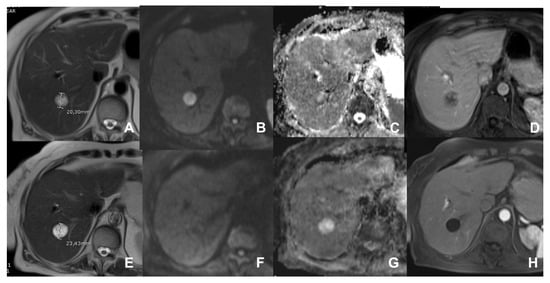

| Cirrhotic liver: characterization of FLL/Follow-up after treatment | HASTE T2 | AXIAL | -- | -- | Anatomy and liquids analysis |

| INDICATIONS: MRI is the technique of choice in young patients and pregnant women after a unclear US finding. Moreover, it is useful even after a CT with undefined diagnosis for all patients. | HASTE T2 | CORONAL | -- | -- | Anatomy and liquids analysis |

| DWI b 0–50–400–800 | AXIAL | -- | -- | High signal in b 800 suspicious for HCC | |

| GRE T1 IN/OUT | AXIAL | -- | -- | Steatosis | |

| GRE T1 3D DYNAMIC | AXIAL | PRE-ART 25″-PORTAL 70″-LATE 180″ | YES (if the lesion shows atypical enhancement) | Hypointensity in HBP suspicious for HCC | |